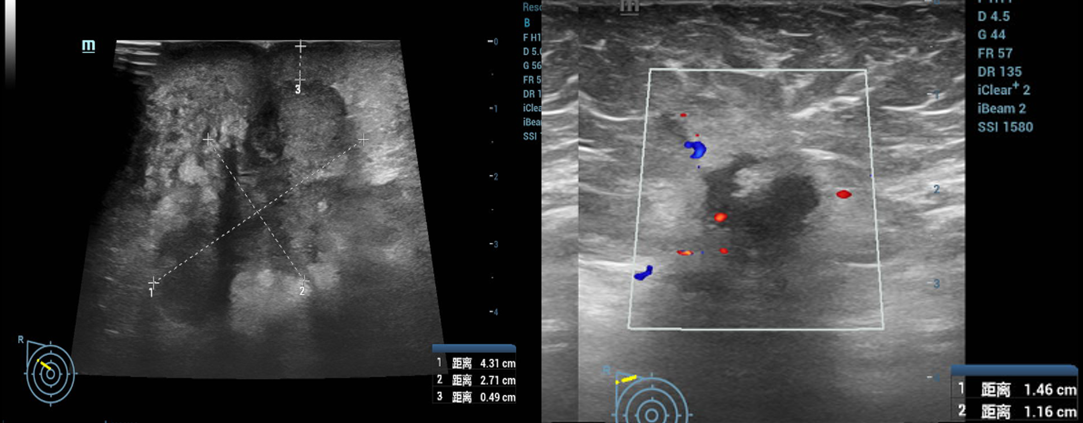

(2025-5-5)乳腺及腋窝淋巴结(双侧)浅表脏器彩超检查:1.右乳腺外上实性占位:考虑乳腺癌(4.3×3.0cm),符合BI-RADS 5类;2.右腋窝多发淋巴结肿大,考虑转移可能(1.5×1.2cm)。

(2025-5-5)乳腺及腋窝淋巴结(双侧)MRI检查:1.右乳外上肿块4.6x5.1×3.9cm,MRI-BI-RADS V类。2.右腋窝淋巴结肿大:考虑癌转移(1.7×1.5cm)。